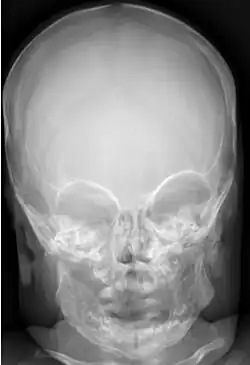

Radiographs initially show layers of periosteal new bone formation with cortical thickening. Periosteal new bone may cover the diaphysis of the bone, causing an increase in diameter of the bone. Over time, the periosteal new bone density increases, becoming homogeneous with the underlying cortex. Eventually, the bone remodels and resumes a normal appearance.

Most infants with infantile cortical hyperostosis are diagnosed by physical examination. X-rays can confirm the presence of bone changes and soft tissue swelling. Biopsy of the affected areas can confirm the presence of typical histopathological changes. No specific blood tests exist, but tests such as erythrocyte sedimentation rate (ESR) and alkaline phosphatase levels are often elevated. A complete blood count may show anemia (low red blood cell count) and leukocytosis (high white blood cell count). Other tests may be done to help exclude other diagnoses. Ultrasound imaging can help diagnose prenatal cases.